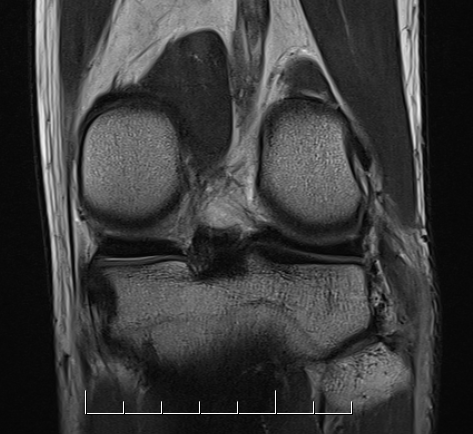

Popliteus

Coronal MRI of left knee demonstrating femoral avulsion of popliteus